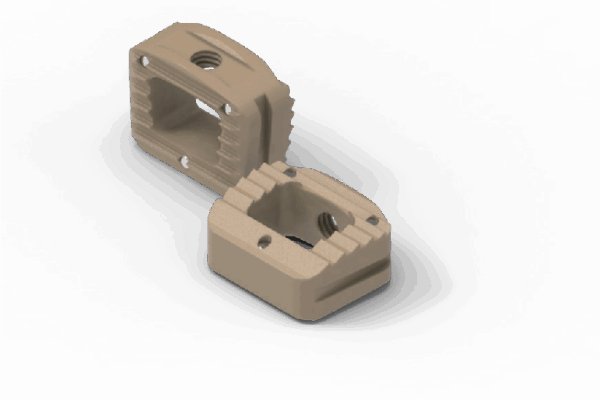

Coales Interbody Fusion Cage System

Cages anatômicos em PEEK para fusão intersomática espinhal.

Sistema de cages para fusão intersomática, com diferentes modelos (Coales-P, C, M, T, L e Mesh), em PEEK, com marcadores de tântalo para melhor visualização e adesão óssea.

- Materiais: PEEK (ASTM F2026), Tântalo.

- Medidas: Diversas opções de altura, largura e ângulo de lordose.

- Usos principais: Fusão espinhal lombar e cervical, oferecendo estabilidade e suporte biomecânico.

- Tipo de produto: Cages intersomáticos para coluna vertebral.

- Compatibilidade: Compatível com técnicas de fusão TLIF, PLIF, ACIF, etc.

Design anatômico • Radiotransparente • Marcadores de tântalo para visualização • Reduz risco de subsistência